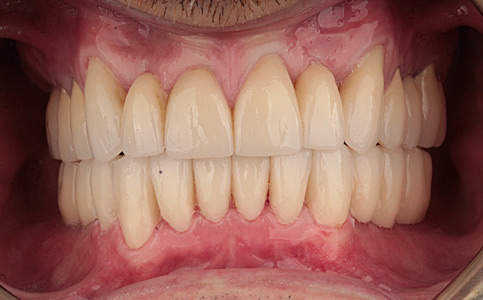

Pacjent zgłosił się do naszego Centrum stomatologii i Ortodoncji FRESHmed w Katowicach w celu poprawnia estetyki swojego uśmiechu. Po konsultacji i dokładnej diagnostyce, usunięto zęby dolne z powodu duzej ruchomości. Zęby zostały zastąpione 6 implantami zębowymi, na których odbudowano cały łuk zębowy dolny metodą All-on-6. Poprawę kształtu i koloru zębów górnych uzyskano poprzez zacementowanie koron pełnoceramicznych.

Zobacz efekty przeciągając suwak w prawo lub w lewo.